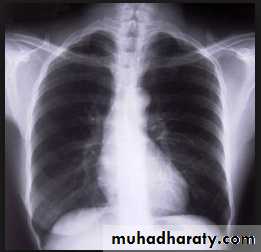

• Alveoiar oedema (‘Bat’s wings’)

• Kerlev B lines (interstitial oedema)• Prominent upper lobe vessels

• Cardiomegaiy

• Pleura

• effusionKerley A lines (Arrows), Kerley B lines (arrowheads)